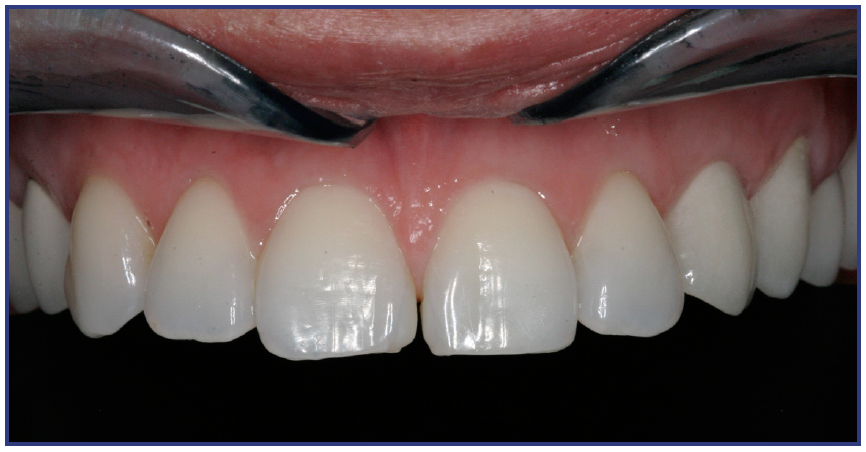

The crown can be cemented or screw retained over the implant. For multiple implant bridge or bar overdenture restorations, the framework try-in appointment is important prior to porcelain build-up or overdenture fabrication to ensure a passive fit, confirmed by an x-ray. Framework trial appointments require a minimal set-up. No anesthetic is required, but a screwdriver for that particular implant system is a must.

The implant prosthesis delivery appointment is similar to that of a crown and bridge. (Figure 22B) If the prosthesis is screw retained, then no cement is necessary and an occlusal filling material, such as composite, is necessary. After bite check, the patient is taught how to maintain the restoration. (Figure 22C)

Figure 22B – Metal-free fixed partial denture cemented on abutments

Figure 22B

Figure 22C – Final smile line

Figure 22C